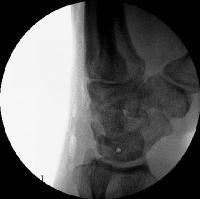

Case 4. Preop dynamic instability

Click for larger image

Lucency where a screw lies.